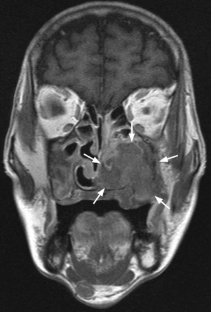

Fig. 2